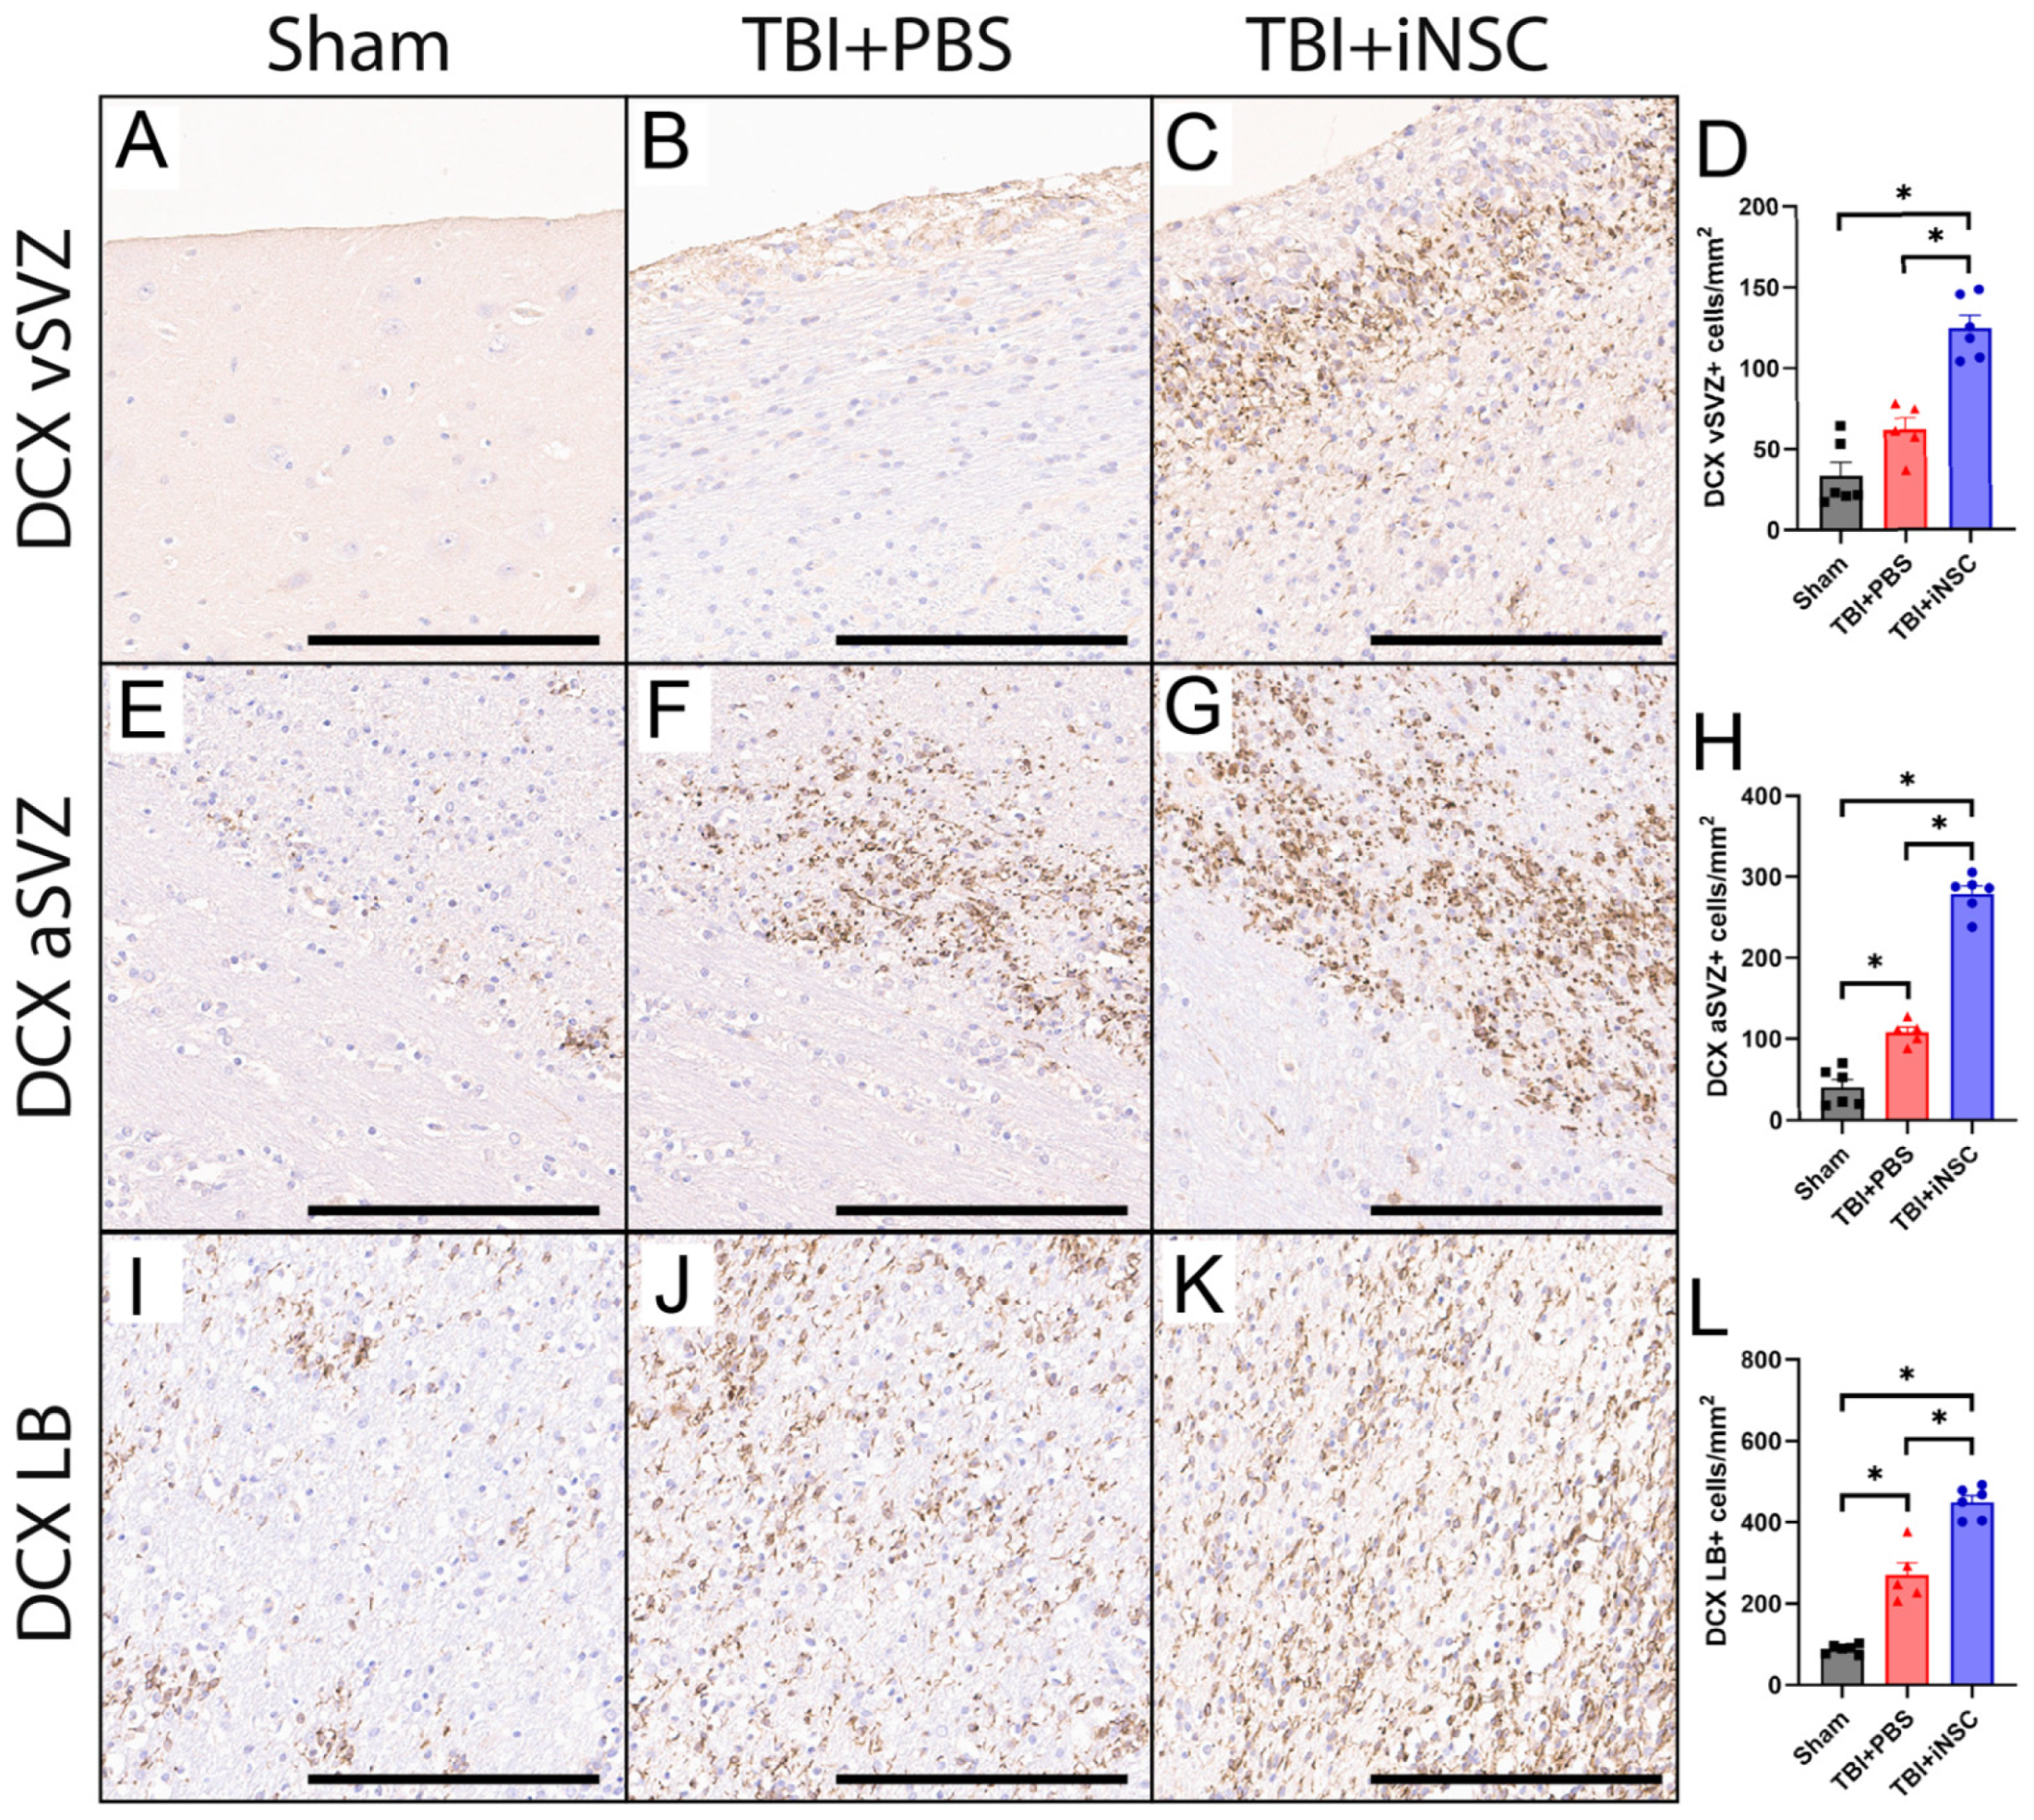

3.3. iNSC Treatment Significantly Increased Neurogenesis Compared to Untreated Piglets